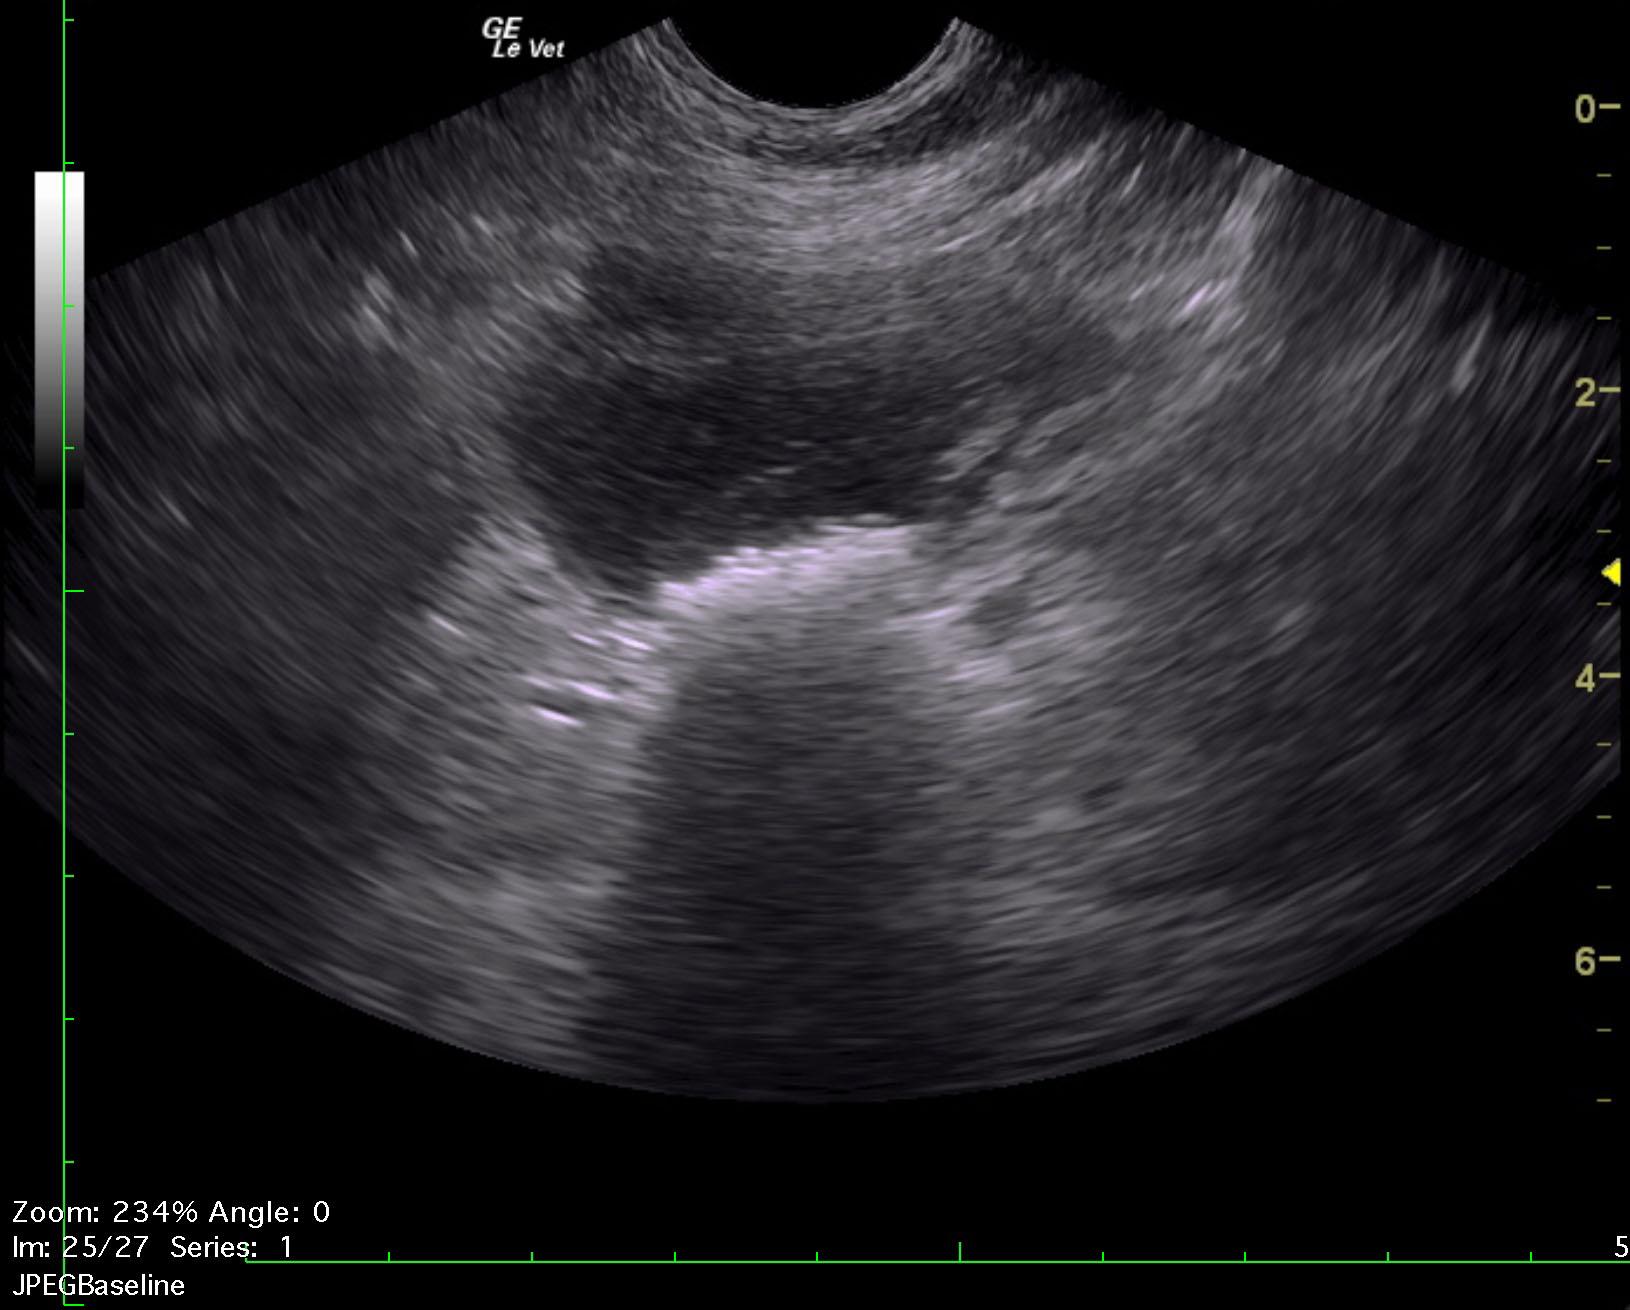

A 10-year-old intact male Komodor with a history of bleeding from the penis was presented recumbent and dyspneic. Abnormalities on CBC and serum biochemistry were leukocytosis, band neutrophilia, monocytosis, azotemia, mild hyperglobulinemia, mildly elevated liver enzyme activity and hyperbilirubinemia.